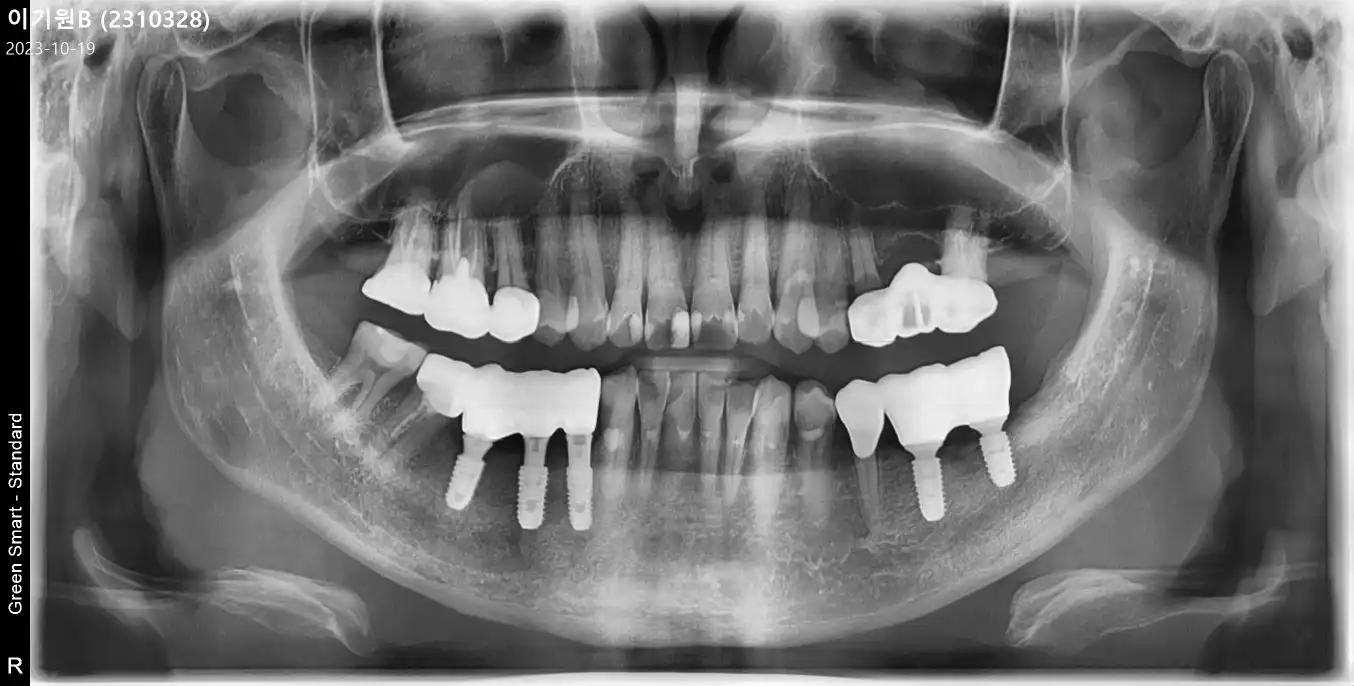

전

후

임플란트 상담 받고 바로 수술 했어요 상담사분들 친절하시구요 이가 많이 안좋아진 상태여서 남편이랑 같이 임플란트 수술 결정 했어요 사람이 많아서 대기시간이 많이 있었지만 수술은 그리 많이 걸리진안았어요 임플란트가 무서워서 너무 늦춰져서 이를 많이 빼야 해서 불편하지만 그래도 후기들많고 많이 찾아오셔서 믿고 했습니다